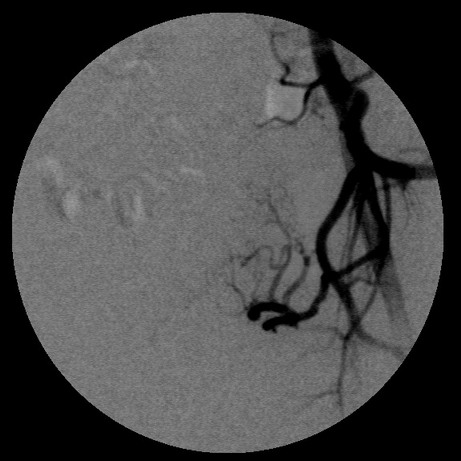

女,35岁,子宫多发肌瘤

子宫动脉增粗,分支数量增多,迂曲,染色明显并排空延迟

要超选到子宫动脉上支吗?